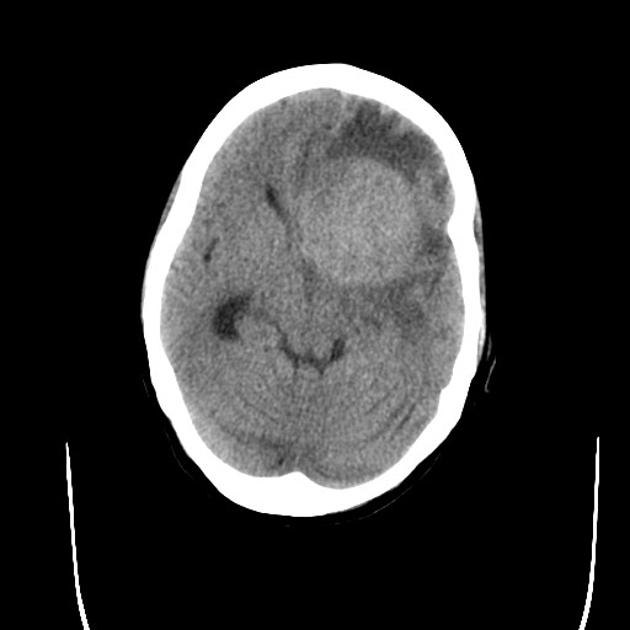

A detailed history and physical evaluation with particular attention to time course and nature of symptoms, followed by an MRI of the brain is the usual initial workup. The T1 MRI shows a hypointense or isointense lesion, and T2/FLAIR shows variable surrounding edema. T1/Gad shows homogenous enhancement without ring enhancement and lacking central necrosis. Ring enhancement occurs more often in immunocompromised patients.

CT images are hypointense. Hemorrhage is uncommon. Multiple lesions are more common in HIV+ patients.